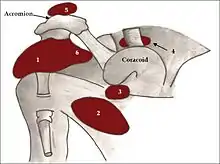

Schéma de l'articulation de l'épaule humaine, vue de face

Bourses synoviales

L'articulation gléno-humérale est entourée de plusieurs bourses synoviales

- la bourse subacromio-deltoïdienne formée de la confluence de la bourse subdeltoïdienne, entre l'articulation et la face profonde du muscle deltoïde, et de la bourse subacromiale, entre l'articulation et la voûte acromiale,

- une bourse synoviale entre le processus coracoïde et la capsule articulaire,

- la bourse du muscle coraco-brachial entre le tendon du muscle coracobrachial et le muscle subscapulaire,

- la bourse bicipito-radiale qui entoure le tendon du chef long du muscle biceps brachial dans le sillon intertuberculaire de l'humérus.et qui communique avec la synoviale de l'articulation.

Au-dessus de l'acromion se trouve la bourse subcutanée acromiale non connectée à l'articulation.